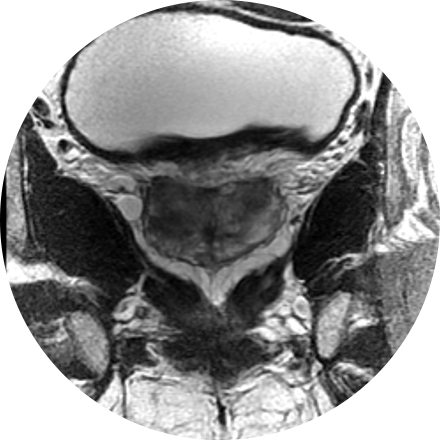

Prostate MRI

Magnetic resonance imaging (MRI) of the prostate uses a powerful magnetic field, radio waves and a computer to produce detailed pictures of the structures within a man’s prostate gland. It is primarily used to evaluate the extent of prostate cancer and determine whether it has spread. It also may be used to help diagnose infection, benign prostatic hyperplasia (BPH) or congenital abnormalities.